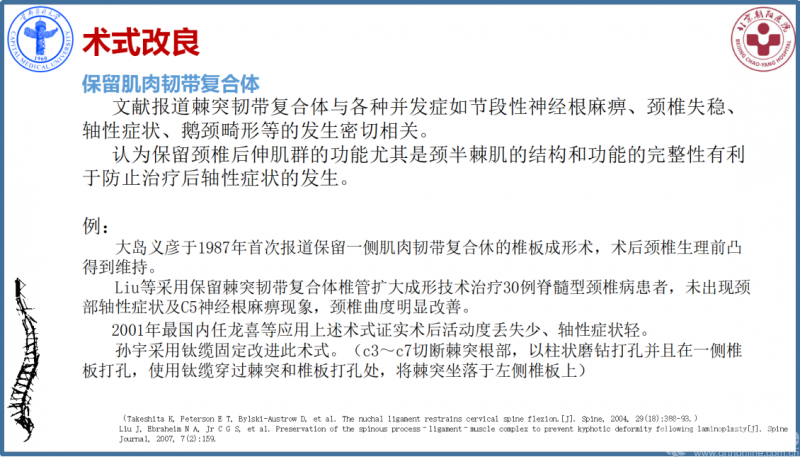

④颈后韧带复合体受到破坏

颈椎后方棘突肌肉韧带复合体的完整性对颈椎的稳定至关重要。实验证实,保留颈椎后方韧带复合体的颈椎管扩大成形术术后生物力学稳定性(特别颈椎前屈时)上明显优于传统术式;术后颈椎曲度、柔韧性以及AS发生率均明显优于传统单开门术。

例:

● Hosono N, Sakaura H, Mukai Y, et al. En bloc laminoplasty without dissection of paraspinal muscles[J]. Journal of Neurosurgery Spine, 2005, 3(1):29.

● Yoshida M, Tamaki T, Kawakami M, et al. Does reconstruction of posterior ligamentous complex with extensor musculature decrease axial symptoms after cervical laminoplasty?[J]. Spine, 2002, 27(27):1414-1418.

● Okada M, Minamide A, Endo T, et al. A prospective randomized study of clinical outcomes in patients with cervical compressive myelopathy treated with open-door or French-door laminoplasty[J]. Spine, 2009, 34(11):1119-26.

常规后路单开门手术会对后方部分韧带复合体、双侧椎旁肌、部分棘突、棘间韧带、棘上韧带进行剥离或摘除,从而破坏维持颈椎生物力学的基本结构,影响颈椎结构的稳定性。故术后颈椎易发生生理曲度丢失,出现鹅颈畸形等并发症;另外由于手术创伤与组织缺损,术后发生广泛的结缔组织填充替代,出现广泛粘连,影响颈伸肌群功能及柔韧性。同时因肌肉附着点未重建,将导致不可恢复的肌肉萎缩,从而出现术后颈背部僵硬、酸胀、乏力、活动受限、活动受限等轴性症状。